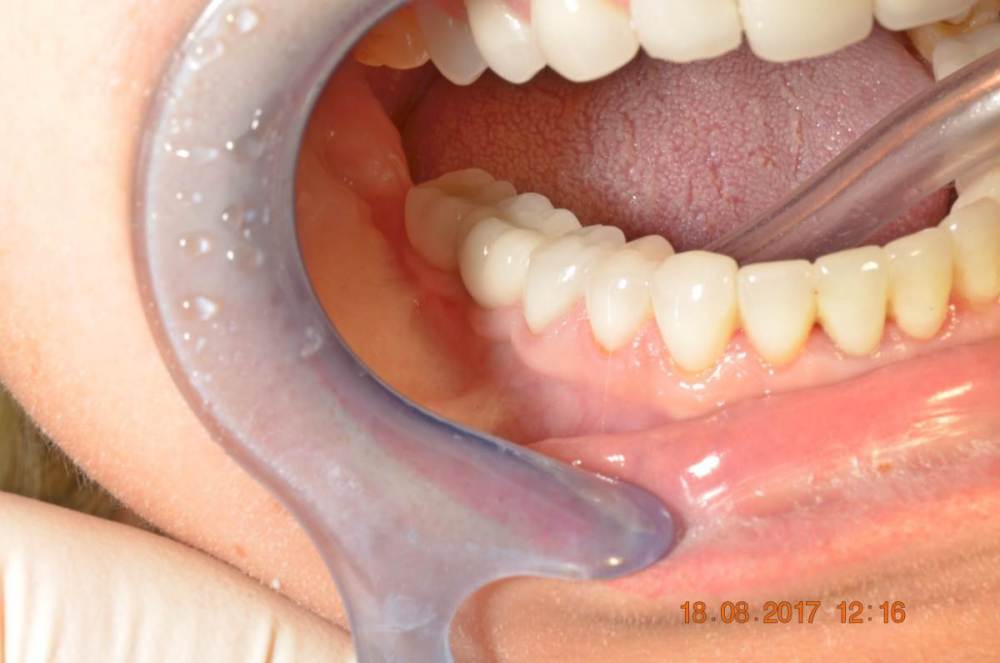

Большой Зеленый Опубликовано 7 ноября, 2022 Поделиться Опубликовано 7 ноября, 2022 Обратите внимание на даты 2 Ссылка на комментарий

Большой Зеленый Опубликовано 7 ноября, 2022 Поделиться Опубликовано 7 ноября, 2022 У Меня много реферативных пациентов . приходят протезироваться на других системах . Фрезерный центр легко изготавливает любые абатменты . Слепочный модуль и аналог купить в эпоху интернета очень просто . Какая нужна распространенность? Ссылка на комментарий

Большой Зеленый Опубликовано 7 ноября, 2022 Поделиться Опубликовано 7 ноября, 2022 У дилера есть премил абатменты. За 10 лет работы проблем никаких не было. 1 Ссылка на комментарий